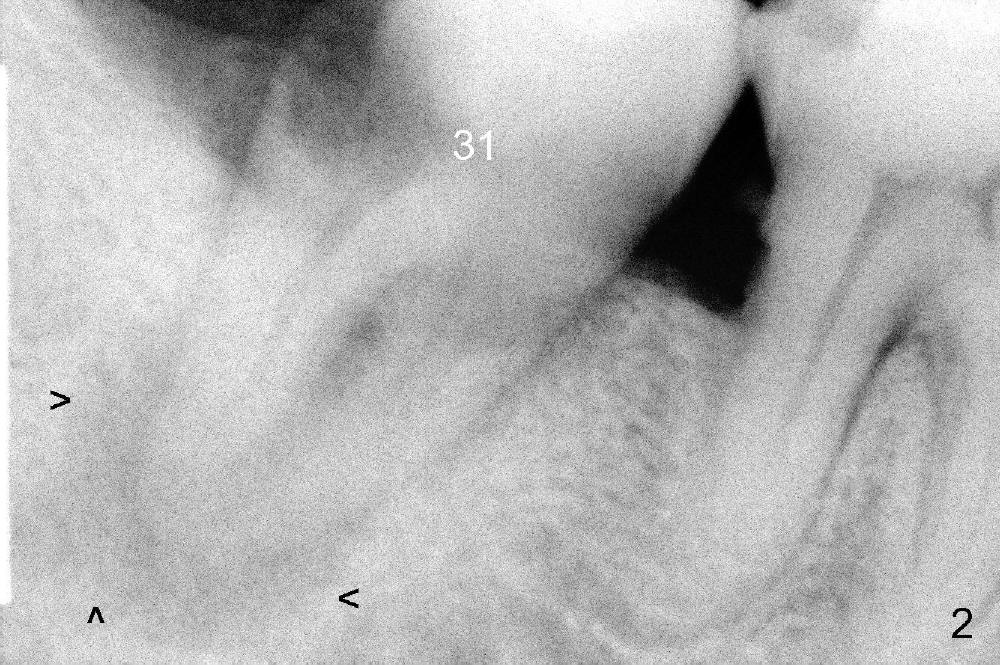

A 52-year-old man (heavy smoker) presents to office without schedule. He has severe pain at #31 and wants extraction immediately (Fig.1,2). He likes the idea of immediate implant, but we do not have time for it that day. Therefore the tooth is extracted (Fig.3). The socket is single. After debridement, bone graft (Fig.5 *) and collagen membrane (Fig.4) are placed.

The patient will return for implant placement 2.5 months post extraction. He must be a gagger, because PAs in Fig.2,5 are taken with sensor 1. The Inferior Alveolar Nerve is out of view. It appears that he is too busy to have CBCT taken in the other office.